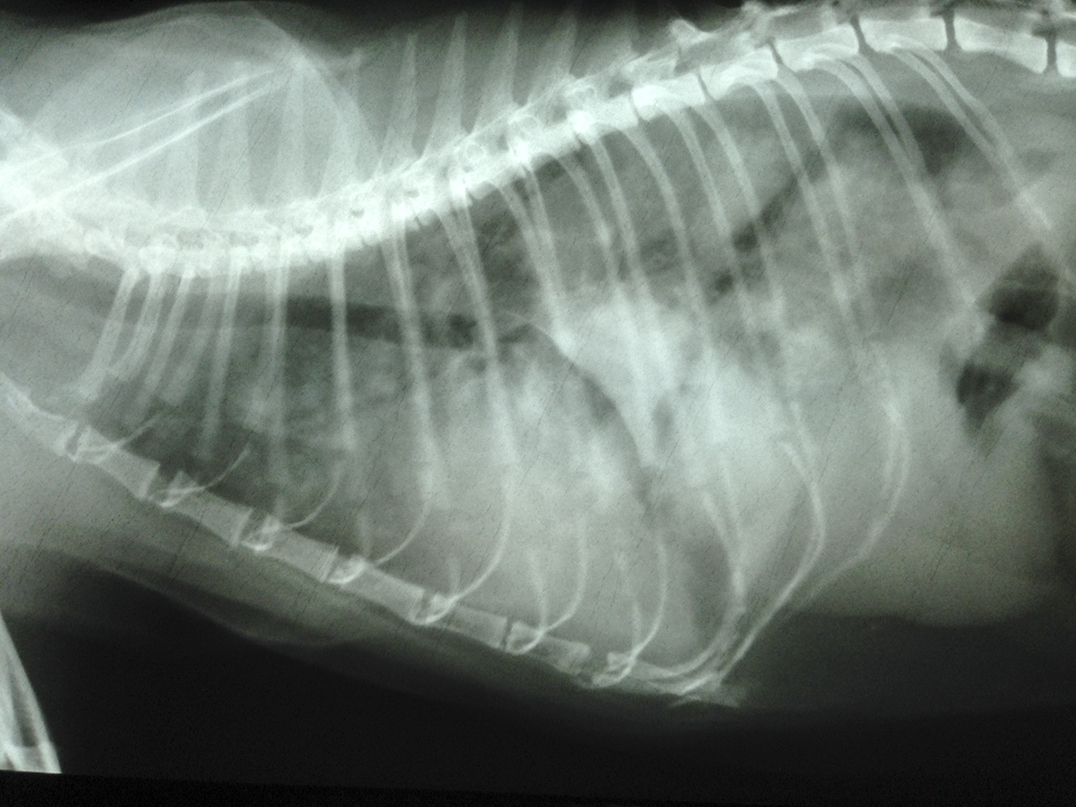

This winter, two of this reporter’s Sheguiandah neighbours had pets that succumbed to blasto—a cat and a puppy. In the case of the cat belonging to Chrissy Wade, animal activist, her mother Joanne explained that after a busy Christmas holiday and with members of the household away for a few days, she returned to find a very sick, lethargic cat (named Seneca) who was having trouble breathing. She was brought to the Island Animal Hospital and overseen by Dr. Johanne Paquet and, following a chest x-ray that showed her lungs were filled with yeast, Dr. Paquet was able to confirm her suspicions—the cat had blastomycosis. The cat’s health was so far gone that it was unlikely she would have survived but the Wades started their beloved pet on the itraconazole treatment with the hope that she would recover. Sadly, the cat died days later. An autopsy showed Seneca’s lungs were indeed filled with blasto lesions and the pet’s advanced infection had placed her beyond recovery. Within months of Seneca’s passing fellow neighbour Melanie Francis’ puppy also contracted the disease. The puppy also died soon after.

At this same time our cat Rudy, a big strapping fellow with a love of food, was becoming ill. He had already been treated for a wound on his front leg that required minor surgery and antibiotics, but it wasn’t getting better. Back for another trip to see his vet, Dr. Paquet, and the concern of blasto was mentioned. A chest x-ray showed spots on his lungs and a sample from a lesion found on his head also confirmed the news—the little purple figure eights of yeast showed Rudy had blasto, likely because of the backyard construction. He was immediately placed on itraconazole and given a 30 to 50 percent chance of survival. This was two weeks ago.

courtesy of Island Animal Hospital

After the diagnosis, Gordonach’s breathing, at its worst, was almost one breath per second, she explained. The dog’s chest x-ray revealed what looked like “a snowstorm” of yeast. Because of the seizure, the golden doodle was also placed on phenobarbital as well as the anti-fungal itraconazole.